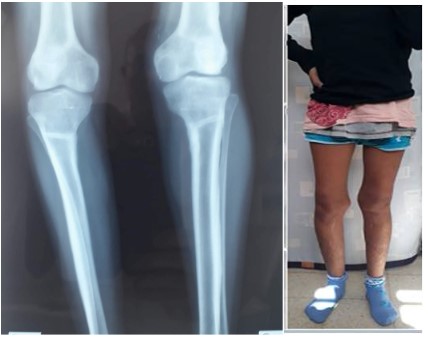

Six months following surgery, patient seems very satisfied, walking with no limping, with a full range of knee motion (0/130°). Clinical correction was confirmed by plan lower limb x- ray showing a neutral mechanical axis and completely healed osteotomies (Figure 4).

Figure 4: Clinical and radiological results at the last follow-up with correction of limb mecanic axes.